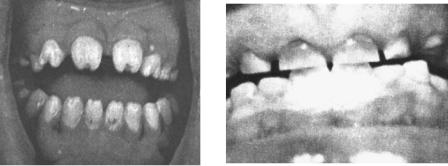

нерализация. Различают гипоплазию системную и местную (рис. 3, 4). Закладка молочных зубов начинается на 4 – 8-й неделе внутриутробного развития плода, их дифференцировка – на 12 – 14-й неделе, минерализация – на 17 – 18-й неделе. При системной гипоплазии молочных зубов этиологическим фактором является нарушение обменных процессов в организме беременной женщины (прежде всего водно-солевого, белкового обмена). Эти нарушения чаще всего связаны с такой патологией, как токсикоз беременности, нефропатия, ревматизм, эндокринная патология, резус-конфликт, а также с воздействием факторов внешней среды и др.

Рис. 3: Системная гипоплазия

Рис. 4: Гипоплазия резцов